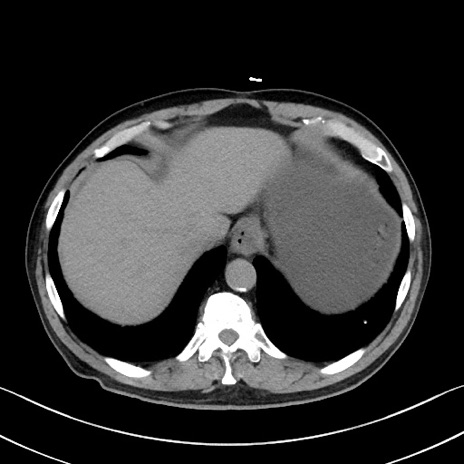

症例35(横断像)

【症例】70歳代 男性

【主訴】腹部膨満、嘔吐

【現病歴】昨日より腹部膨満感出現。本日増悪し、仙痛出現。嘔吐あり、受診。

【既往歴】糖尿病、胆摘後

【身体所見】BP 149/80mmHg、HR 74/min、BT 35.9℃、腹部:膨満、軟、圧痛なし。腸雑音減弱あり。上腹部正中切開瘢痕あり。

【データ】WBC 13500、CRP 1.72